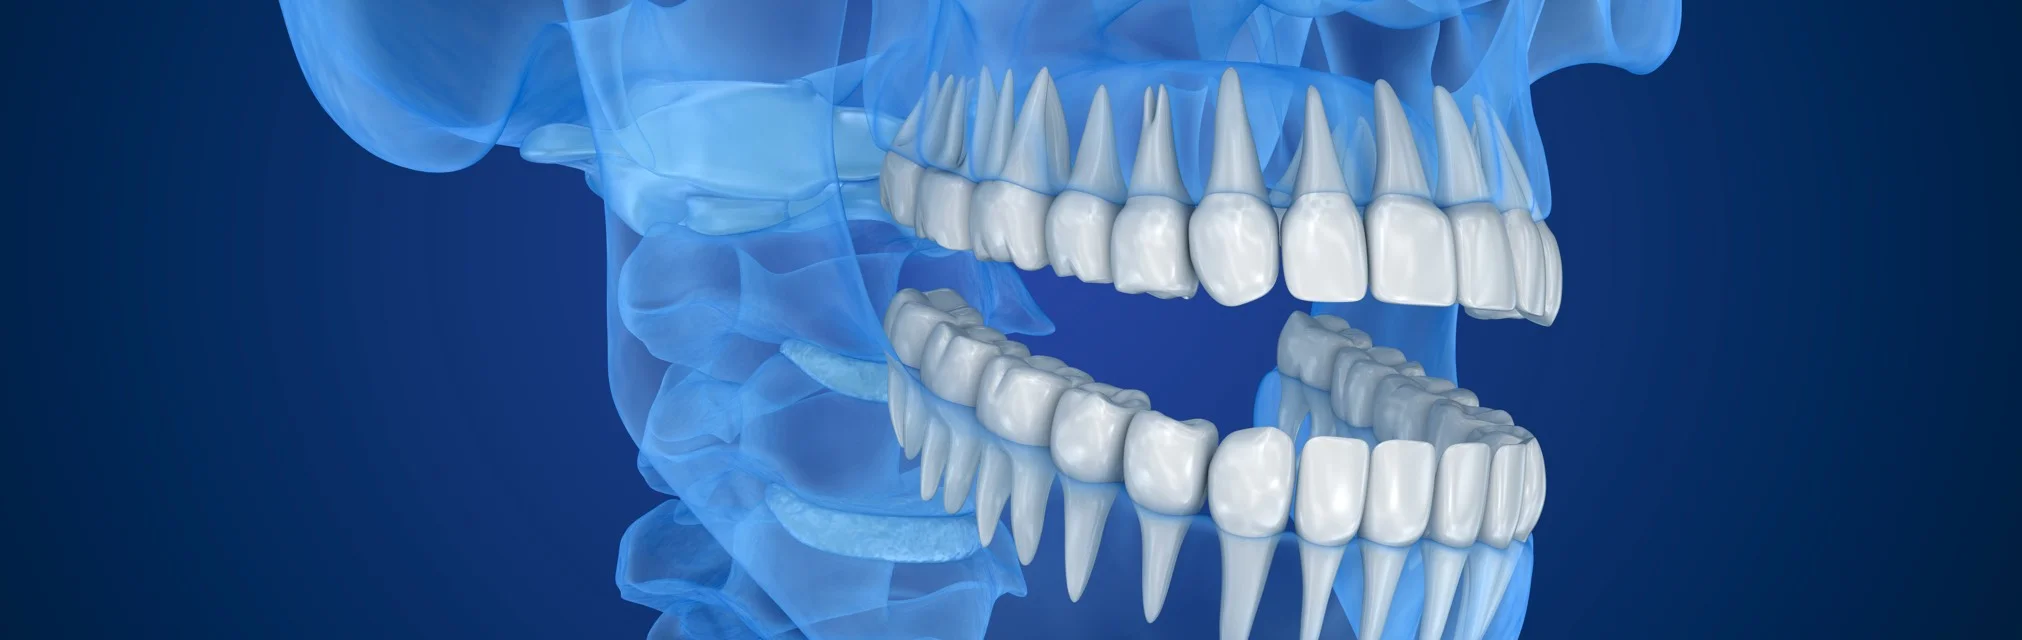

3D снимки позволяют стоматологам рассмотреть зубы под разными углами.

Врач изучает 3D снимки на компьютере и в отличии от 2D снимков, он может крутить изображение под любым углом, который ему необходим, заглядывать «внутрь» каждого зуба.